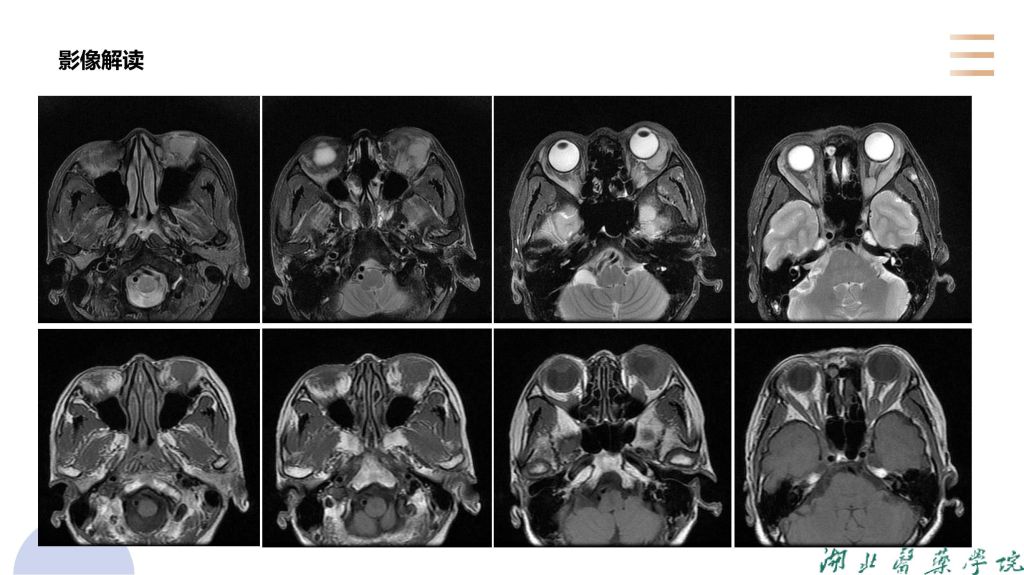

病例分析-眼眶淋巴瘤